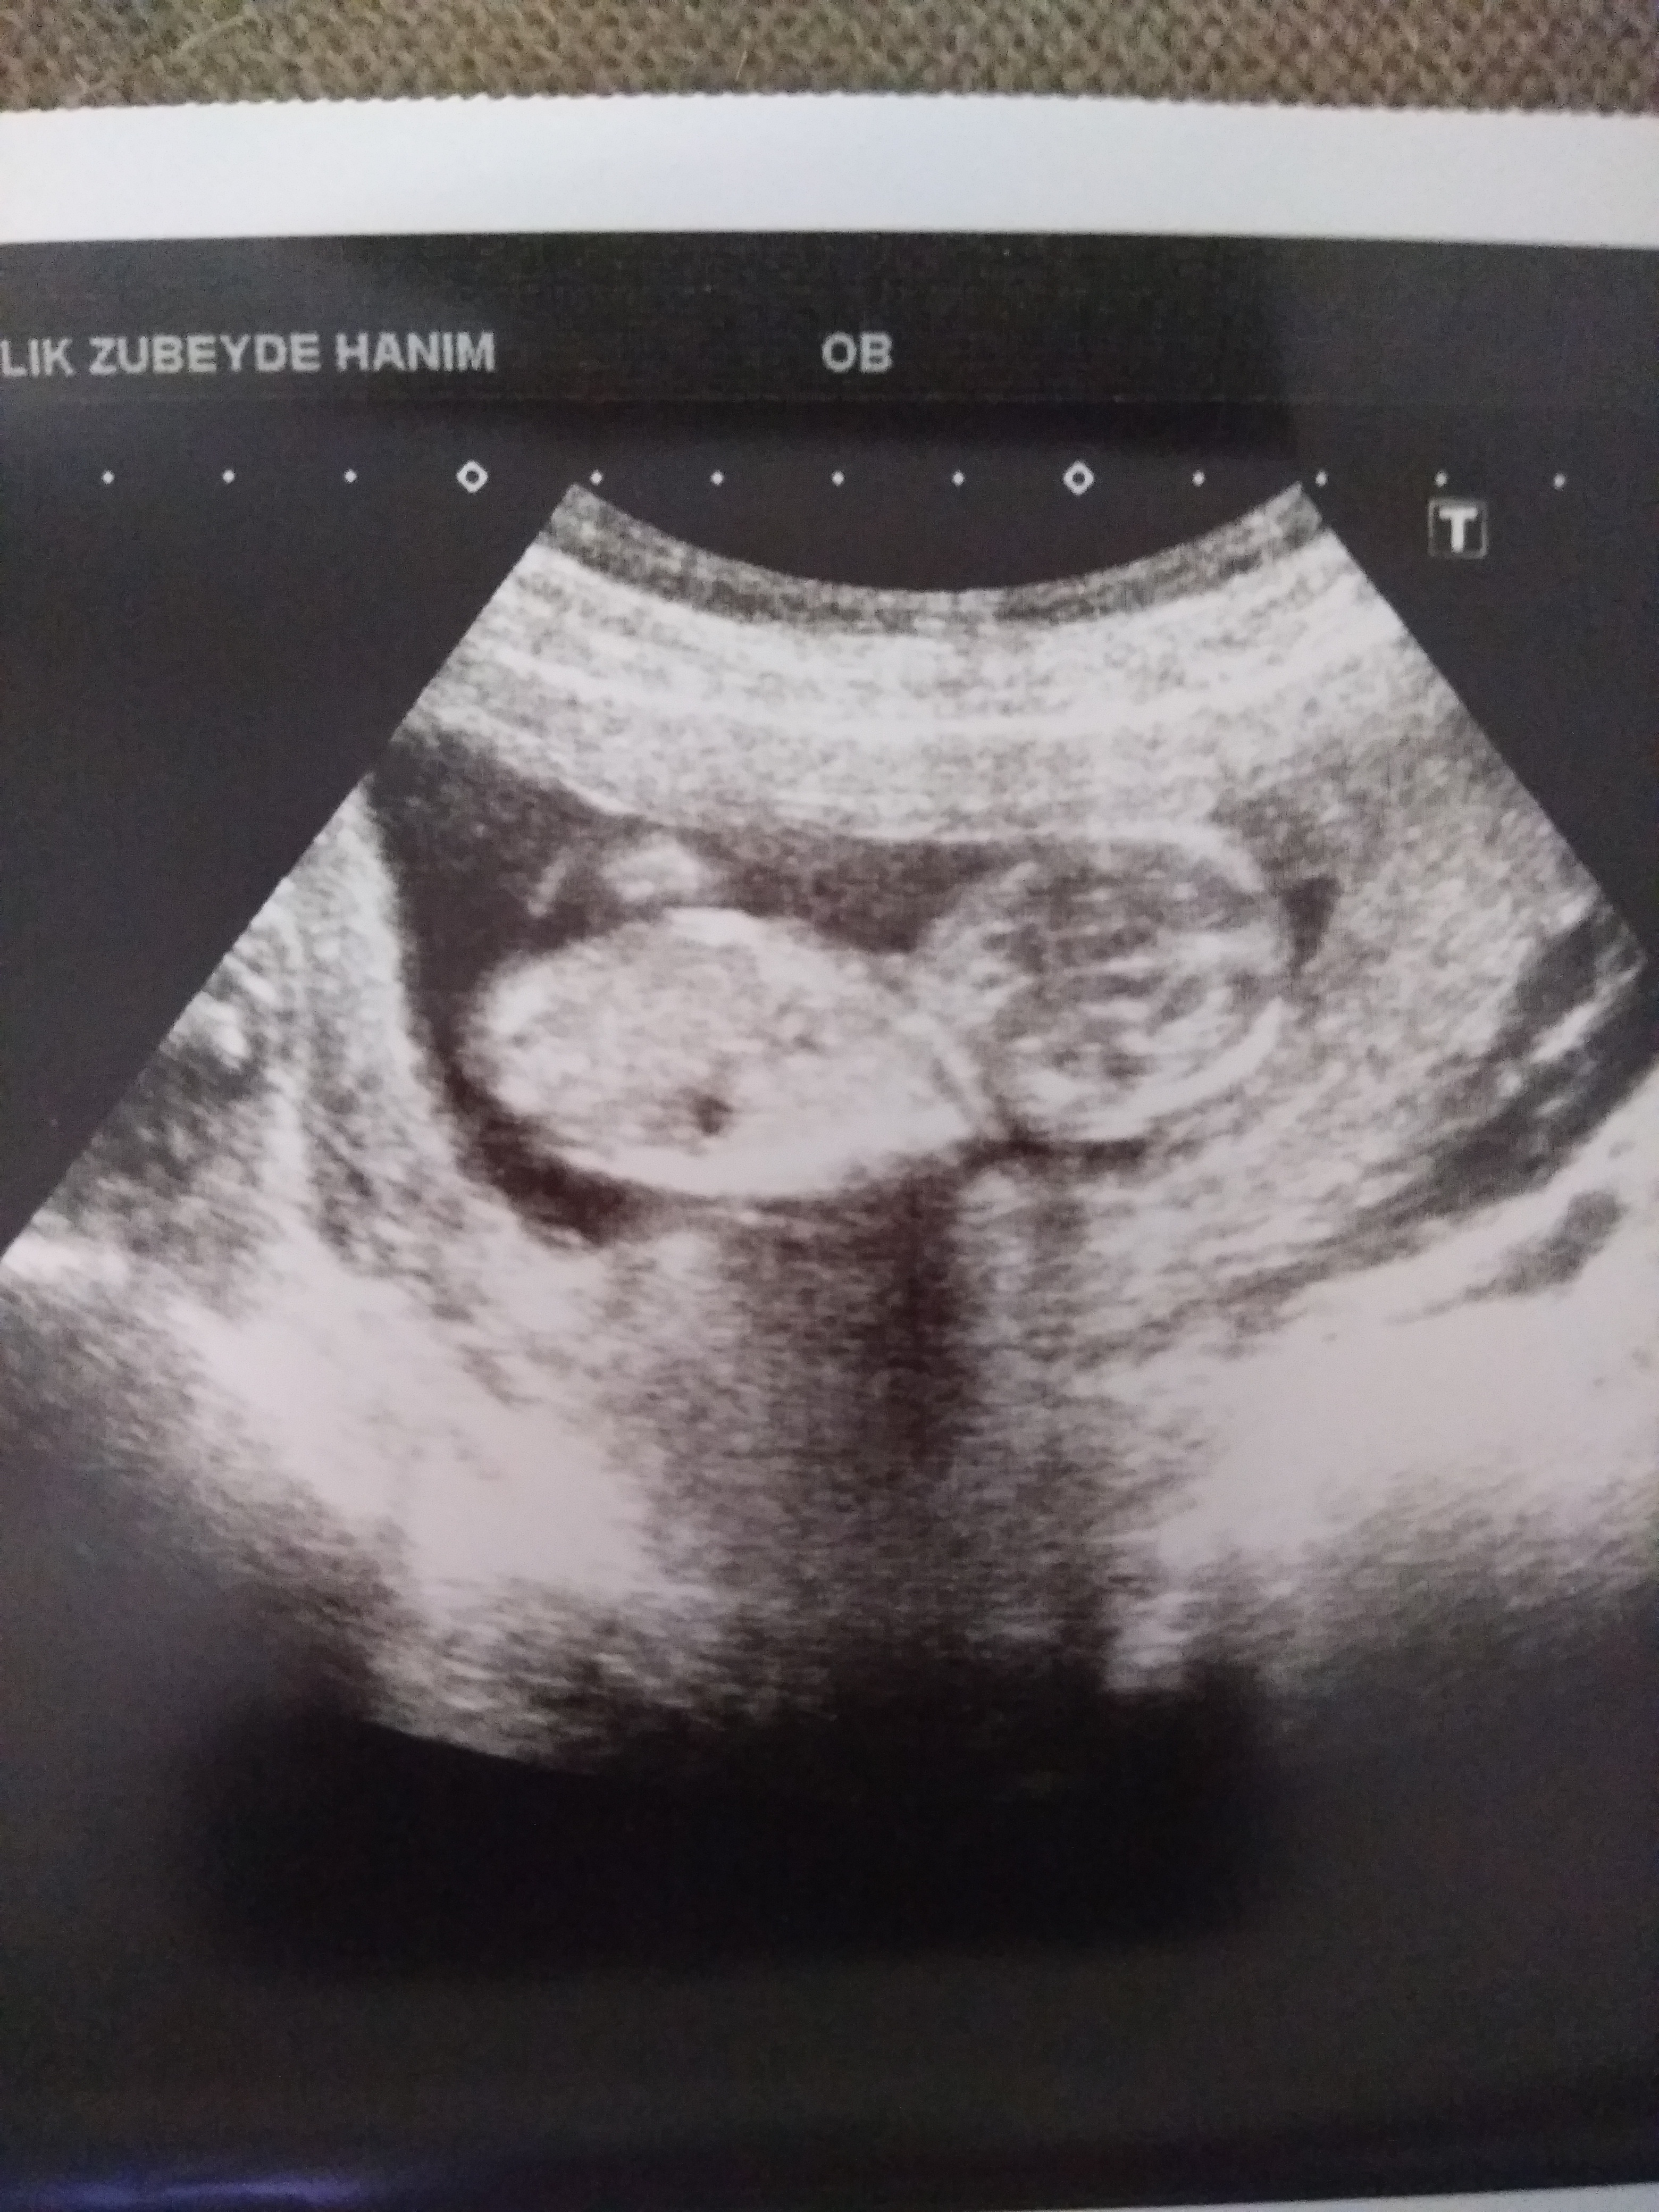

Merhaba sanırım siz daha öncede aynı görseli yüklemiştiniz . Görsellerde nub çıkıntısı belli değil arkadaşım . Bu yüzden bebeğinizin cinsiyetini tahminde bulunamıyoruz maalesef.

Merhaba , görselin değerlendirilmesi için görselin net görüntüsü ve nub çıkıntısının belirgin olması lazım . Aşağıda yer alan linkteki görseller gibi. Linki ziyaret edip görselleri inceleyebilirsiniz.